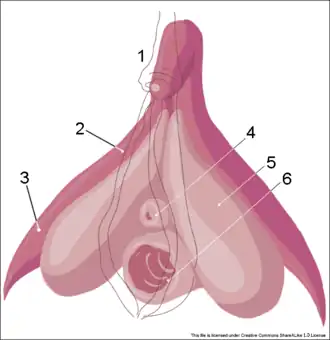

-

Skizze der eröffneten Vulva (oberer Teil) und Vagina (unterer Teil). Blick auf das Innere der Vagina (von ventral) und dem Muttermund (Portio vaginalis uteri)

Skizze der eröffneten Vulva (oberer Teil) und Vagina (unterer Teil). Blick auf das Innere der Vagina (von ventral) und dem Muttermund (Portio vaginalis uteri) -